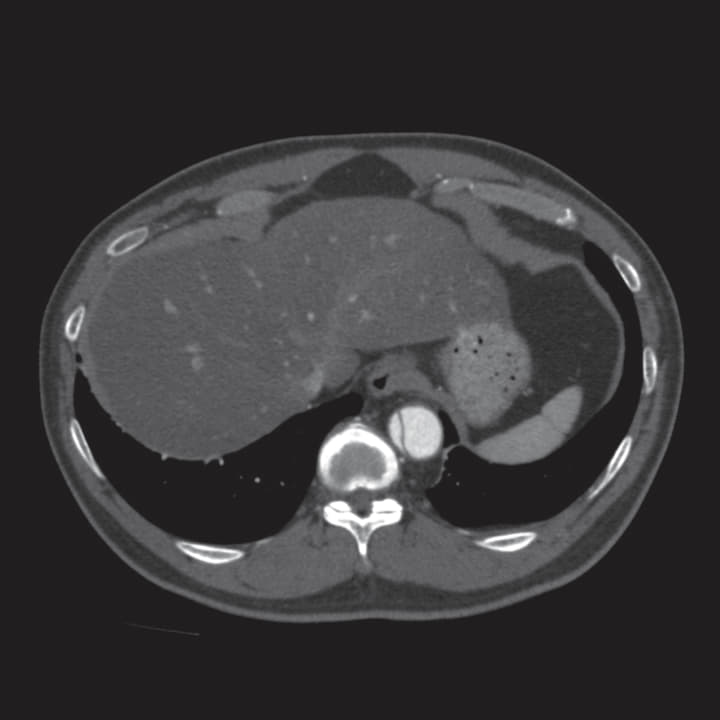

エントリーはT5レベルにあり大きさは29 mm、Zone 3大弯側の解離腔には比較的厚い(13 mm)偽腔内の血栓を認めたため、Zone 2ランディング+デブランチ(Ax-Axバイパス)の方針とした。

中枢は Zone 2の血管径32.0 mmに対して径34 mmのデバイスを選択し、末梢留置位置は下行大動脈が直線化しているTh12レベルへ、発症後1年以内であることからリモデリングを期待し、同部位真腔長径のおおよそ130%である26 mm デバイスを選択した(末梢31 mm/26 mm 10 cmテーパー、中枢34 mm/34 mm 20 cm積み上げ)。

術中術後に主要な有害事象は認めず、術後5日目に退院。術後CTでは遠位弓部偽腔の血栓化を認めた。また、術後6か月の単純CTでは胸部下行大動脈の著明なリモデリング(真腔拡大、偽腔縮小)を認めデバイスの末梢レベルではほぼ偽腔は消失した。